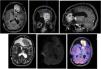

Presentación del casoMujer de 40 años con QE intracraneal de larga evolución que desarrolla una lesión intraaxial rápidamente progresiva de acuerdo con dicho tumor. Tras la resección el diagnóstico es de linfoma primario difuso de células B.

Case presentationA woman 40 years old, harbouring a EC for more than 20 years, develops a fast growing brain lesion next to the EC. Surgery was performed and diagnosis was primary diffuse B cells lymphoma.